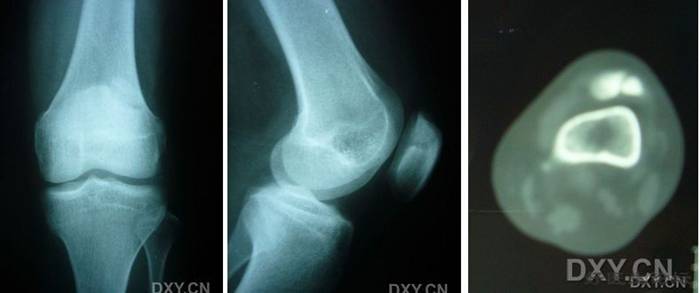

影像学检查

5.jpg

X线摄片

a、常规三个位置 1、正位(前后位) 2、侧位 3、髌股关节轴心位

b、髁间窝位或隧道位 屈膝40°~50°后前位 股骨髁骨软骨炎

c、站立 (负重)位 – 骨关节炎

* CT

* MRI

6.jpg